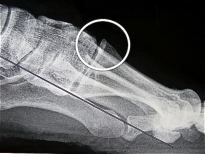

Une arthrose vraie avec la formations de becs osseux (ostéophytes) est rare.

bec métatarsien avec arthrose débutante |

arthrose évoluée avec bec osseux dorsal |